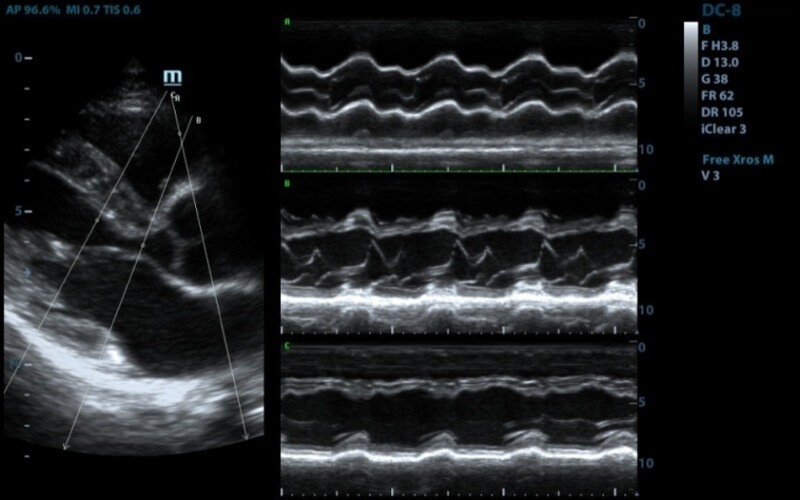

М-режим, одномерный

Такой режим работы УЗИ обычно используют для проведения кардиологической диагностики. Он отображает на экране ткани сердечной мышцы в движении. Это даёт возможность оценить их упругость и эластичность.

Подходит для проведения исследований в трёх форматах:

• M-mode или стандартный — этот динамический режим позволяет получить одномерное изображение.

• Color M-mode или цветной — предполагает одновременное использование стандартного режима и цветного допплеровского картирования. Так в дополнение к серошкальному специалист получит цветное изображение.

• Free-angle M-mode или анатомический — применяют для смены угла вращения и визуализации тканей сердца в различной проекции.

Проведение процедуры предполагает правильное размещение пациента и датчика, чтобы работа папиллярных мышц не исказила результаты.